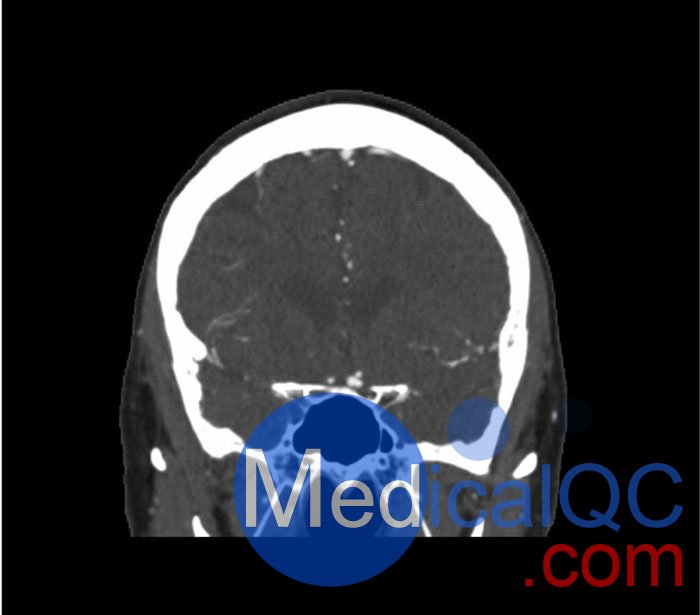

WEK50-03動脈瘤頭模,WEK50-03血管造影CTA頭模是頭部 CTA 動脈瘤模型

模擬造影劑動脈期頭部增強(CT血管造影)。 它覆蓋了頂點枕骨大孔。

模型有三個顱內(nèi)動脈瘤

大腦中動脈 (MCA) 的前部

交通動脈 (ACoA) 和基底動脈動脈。

WEK50-03動脈瘤頭模,WEK50-03血管造影CTA頭模影像圖:

更多效果和DICOM數(shù)據(jù)請聯(lián)系我們

SAG: